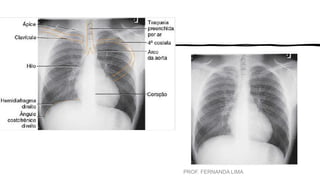

A anatomia radiográfica do tórax é divida em três seções:

•caixa torácica,

•sistema respiratório

•mediastino.

ANATOMIA

• A CAIXA TORÁCICA fornece uma estrutura de proteção.

• Esterno tem três divisões.

• Manúbrio, corpo, processo xifoide.

• Duas Clavículas

• Duas Escápulas

• 12 pares de costelas que circundam o tórax.